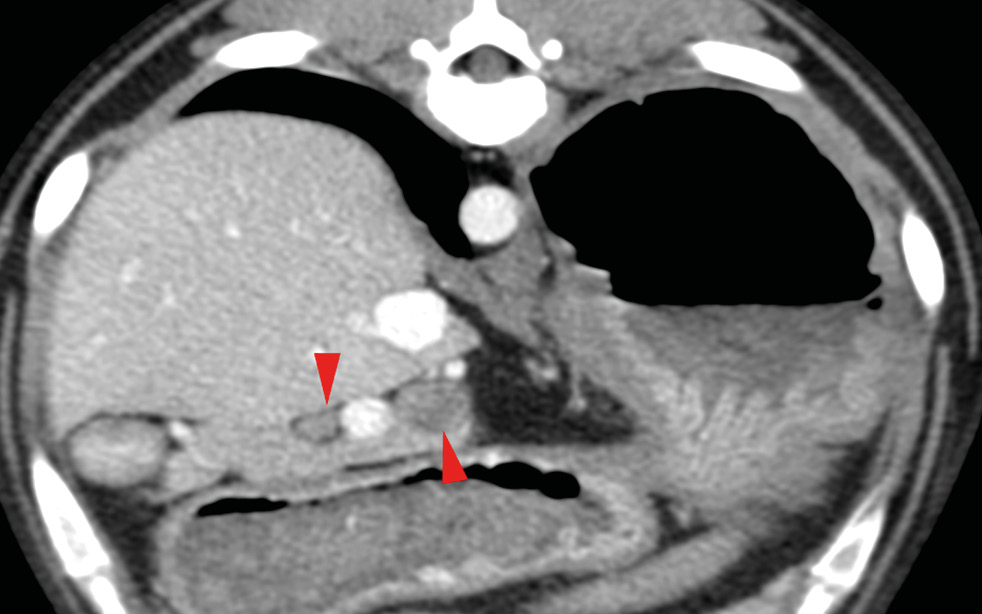

El tratamiento quirúrgico es el de elección para perros con enfermedad en estadio I (enfermedad localizada) o II (presencia de metástasis locorregional) e implica una pancreatectomía parcial para extirpar el tumor primario y cualquier metástasis visible (imágenes 4A-4K y 5A-5H). La mediana de supervivencia es más larga en los perros tratados quirúrgicamente en comparación con los perros tratados médicamente, como se describe en dos estudios donde la mediana del tiempo de supervivencia de los perros sometidos a pancreatectomía parcial fue de 381 días y 785 días, respectivamente, en comparación con 74 días y 196 días, respectivamente, en aquellos tratados solo con tratamiento médico.30 En otro estudio reciente, el tiempo medio de supervivencia registrado para 49 perros con insulinoma fue de 561 días y de hasta 746 días para perros que tuvieron resolución de hipoglucemia, con un tiempo medio euglucémico global (tiempos desde la cirugía hasta la primera detección de hipoglucemia en cualquier momento después de la cirugía) de 424 días para todos los perros.39

Imágenes 4A – 4K. Secuencia de imágenes quirúrgicas en un perro (con las imágenes del TC), durante una pancreatectomía total del lóbulo izquierdo y cuerpo del páncreas (usando la técnica de “guillotina” sutura/fractura con el nudo de Miller modificado) y resección de NNLL centinelas, por insulinoma en el cuerpo del páncreas.

Imágenes 5A – 5H. Secuencia de imágenes quirúrgicas en un perro (con las imágenes del TC), durante una pancreatectomía total del lóbulo derecho y parte del cuerpo del páncreas (usando la técnica de “guillotina” sutura/fractura con el nudo de Miller modificado) y resección de NNLL centinelas, por insulinoma en el lóbulo derecho del páncreas.